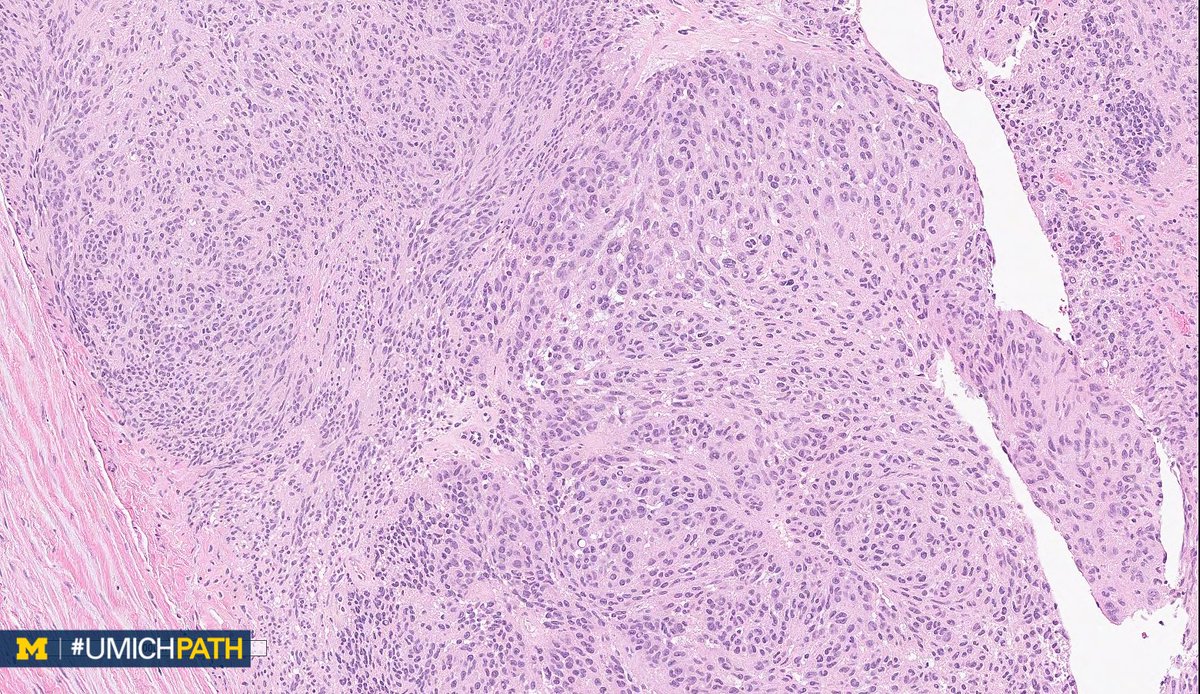

Bone and Soft Tissue #Pathology, day 2

What's your #DifferentialDiagnosis of this superficial soft tissue mass?

What #DailyDx do you favor, and what confirmatory stain(s) would you order?

We’ll tweet the answers and some quick facts tomorrow! #UMichPath#BSTPathpic.twitter.com/BkXUiAuRzg